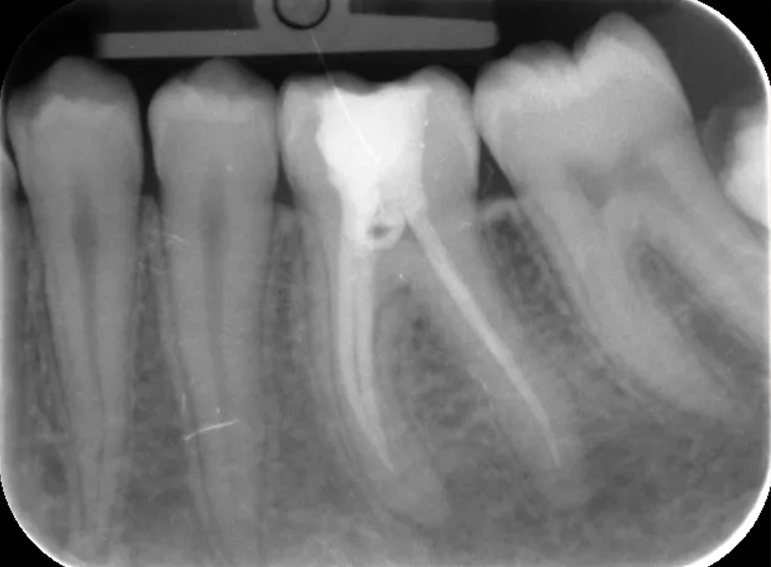

Root filling revision of a lower molar.